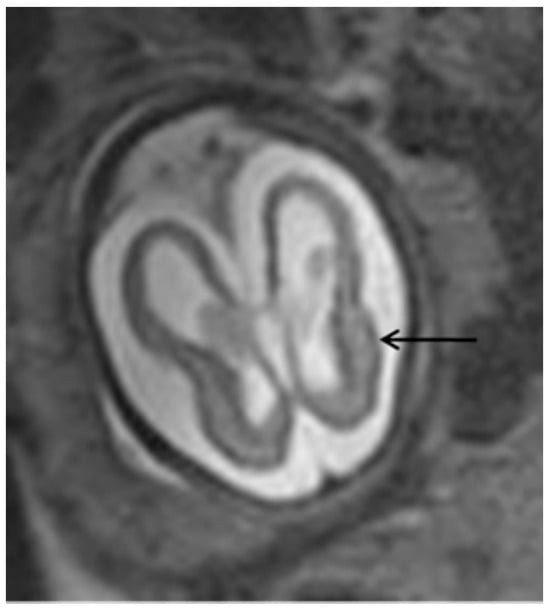

The most common ultrasonographic findings of intrauterine CMV infection are ventriculomegaly, periventricular changes, temporal cysts, and brain parenchymal lesions [25]. Magnetic resonance imaging (MRI) has been shown to complement ultrasonographic imaging in prenatal CMV assessment [25,26]. For example, Buca et al. [26] found that in 6% of ultrasounds in which no CNS abnormalities were seen, the MRIs were positive, but only in cases infected in the first trimester of pregnancy. The abnormalities seen on MRI are the same as those seen on ultrasound, but with a different incidence, with the most common abnormalities seen on MRI being temporal cysts and lesions in the brain parenchyma [25]. (Figure 3) It is known that the additional findings on MRI are due to the lack of studies using multiplanar neurosonography performed by an experienced professional, because when this is method is used, the results of both types of imaging are similar [26,27]. Intrauterine CMV infection is an indication for multiplanar (transvaginal) neurosonography [27]. The main changes seen on neurosonography are abnormal patterns of periventricular echogenicity (suggesting periventriculitis), ventriculomegaly, and echogenic focus in the brain parenchyma [27].

Figure 3.

T2-weighted MRI in axial view of fetal skull showing mild ventriculomegaly and cortical atrophy (arrow).